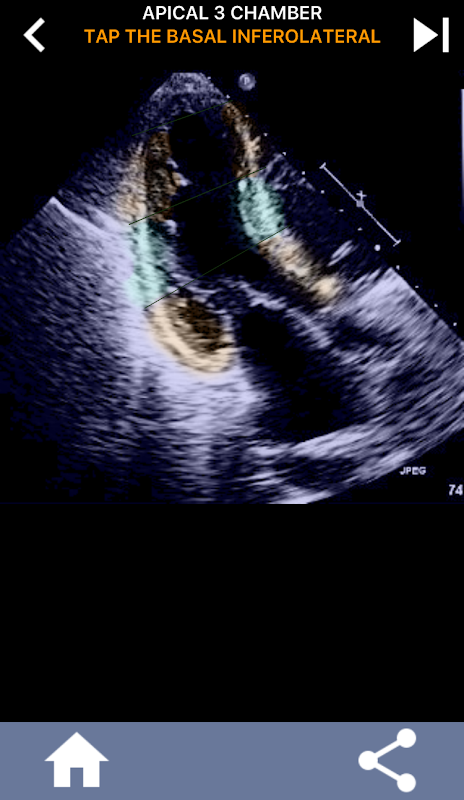

이 응용 프로그램은 AHA로 구분 된 심근을 보여주는 모든 반향보기를 포함하고 올바른 부분을 탭하도록 퀴즈 것입니다. 나는 개인적으로 빨리 반복적 인 퀴즈가 나를 위해 가장 잘 작동한다는 것을 알았다. 나는 주제를 빨리 배우고 암기해야한다. 당신이 에코 / TTE를 공부하는 초음파 학생이라면, 이것은 당신의 연구에 훌륭한 보완책이 될 것이라고 생각합니다.